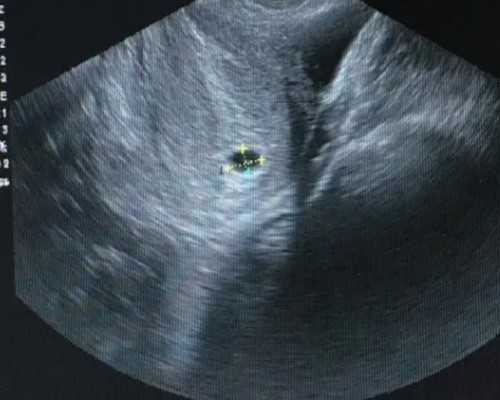

2.B超确认怀孕是否达到45天以上,目前也是香港最快的验血周期了,之前都是七周,也就是49天,随着技术的进步,提前了4天,B超也可以在当地做,带过来即可,也可以过来做,看个人选择,主要是过来做肯定麻烦一点。所以最好在当地做。

孕妇的血液标本被抽出后,首先经过两次高速离心处理,将上层的清液移入新的无菌管内,冷冻保存备用。然后应用试剂将上清液中的DNA提取出来,将其染色,放在在紫外灯下观察。如果看到SRY的条带意味着是男孩,没有则表明是女孩。

3.科学的方法和高的准确率,血液进行Y-DNA进行化验。如果含有y染色体判定为男性,x染色体则为女性。